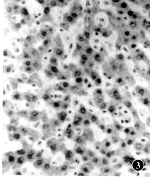

电镜下,腹腔感染动物有毛细胞胆管扩张,微绒毛肿胀、缺失,线粒体嵴变细,排列紊乱,糖原颗粒减少等(图3)。TPN组动物表现毛细胆管扩张,其内有深色胆栓,扩张的毛细胆管周围致密区扩大,有散在的高电子密度颗粒,线粒体肿胀增生,滑面内质网扩张,排列紊乱,可见脂肪颗粒积聚(图4)。

图3 腹腔感染组电镜下示肝脏毛细胆管扩张,微绒毛缺失,线粒体嵴紊乱,糖原颗粒减少 ×2400